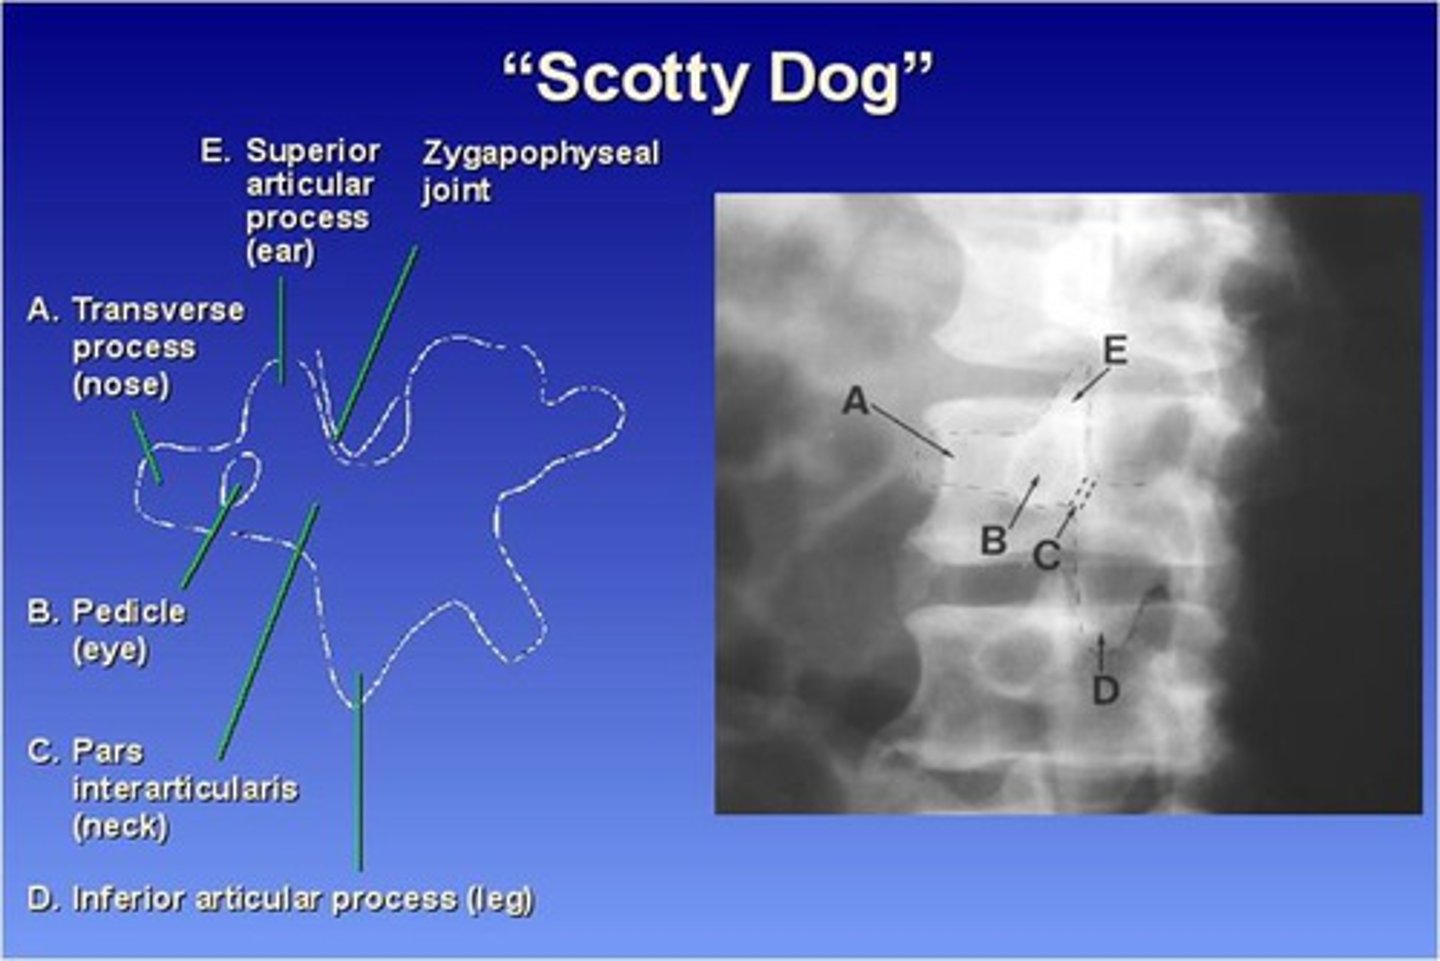

The Lumbar zygapophyseal joints are ONLY demonstrated on what view?

45 degree obliques (will see "scotty dog")

What part of the lumbar spine makes up the "nose" of the "scotty dog"?

transverse process

What part of the lumbar spine makes up the "eye" of the "scotty dog"?

pedicle

What part of the lumbar spine makes up the "neck" of the "scotty dog"?

pars interarticularis

What is the pars interarticularis?

portion of each lamina between the superior and inferior articular processes

What part of the lumbar spine makes up the "leg" of the "scotty dog"?

inferior articular process

What part of the lumbar spine makes up the "ear" of the "scotty dog"?

superior articular process